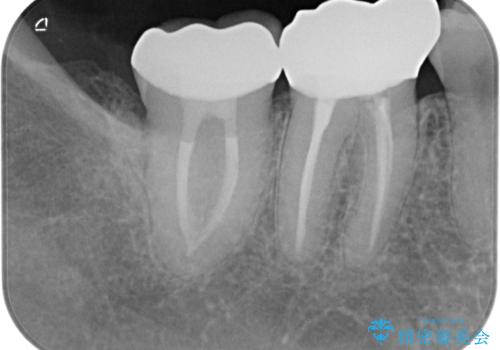

- 冷たいもので長引く痛みがあることを主訴に来院されました。

抜髄を行い、オールセラミッククラウンにて修復を行いました。

根管充填はバイオセラミックシーラーを使用しています。